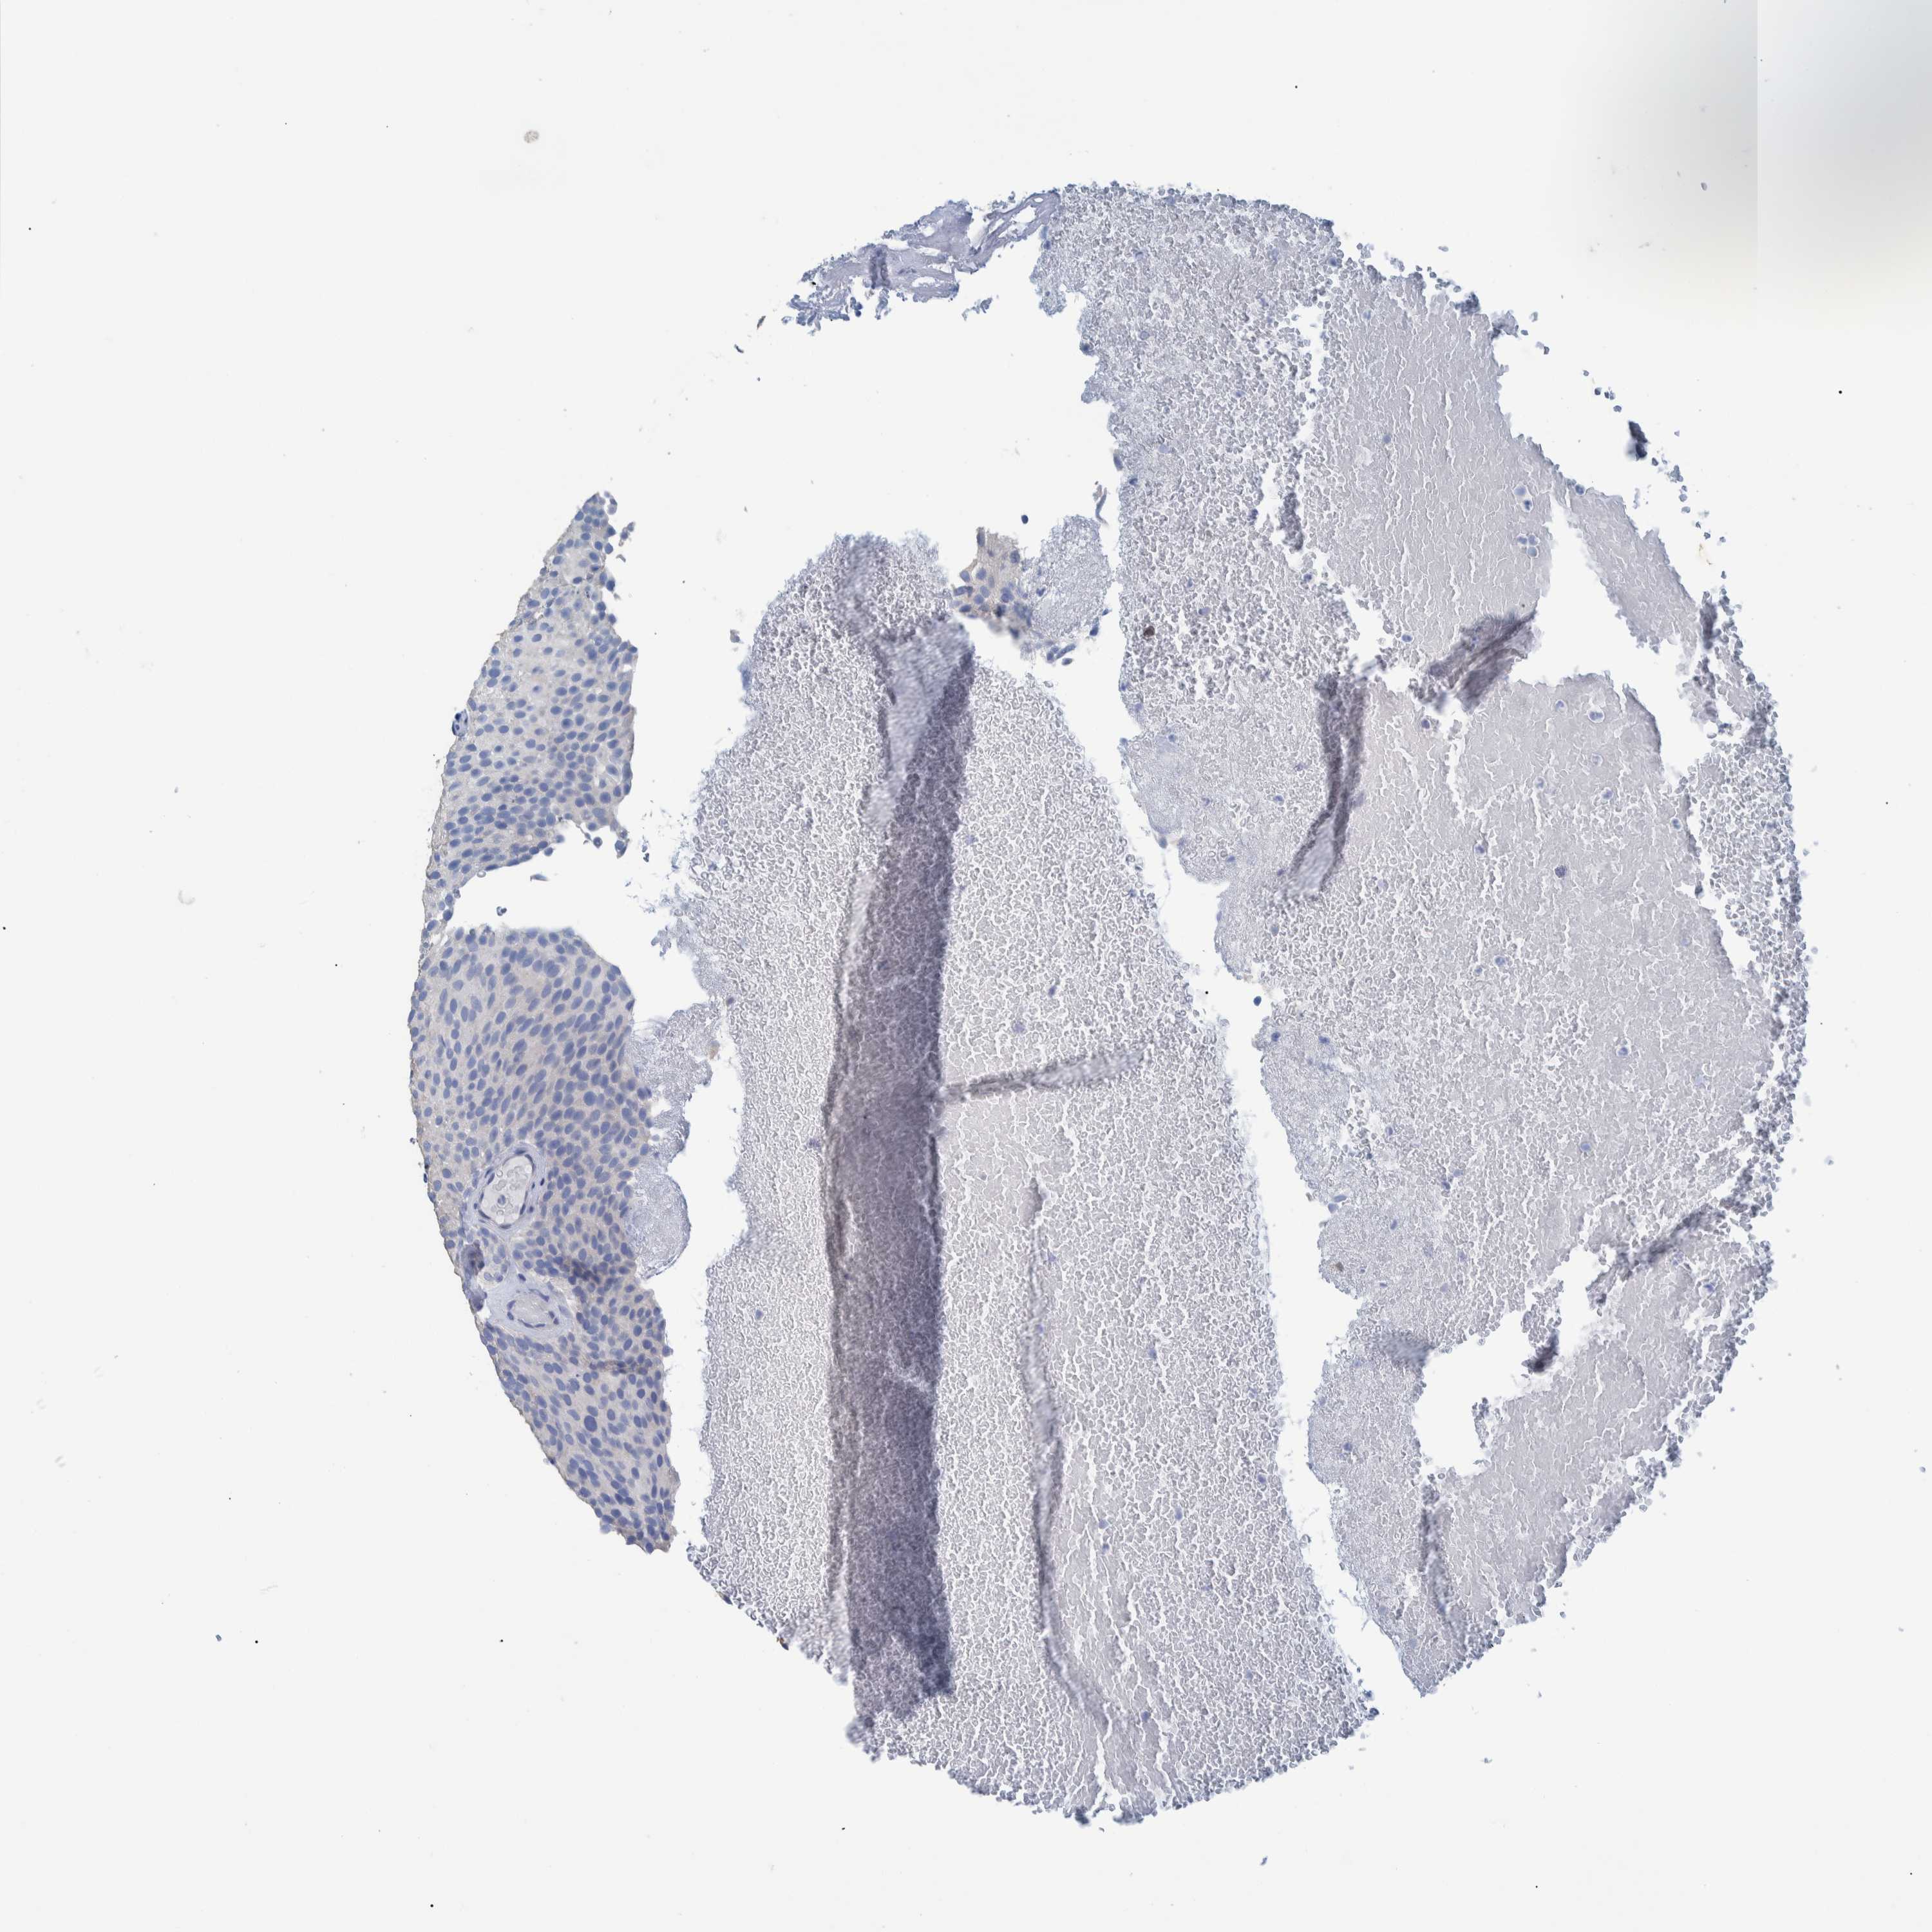

UROTHELIAL CANCER - Protein expressioni

A mouse-over function shows sample information and annotation data. Click on an image to view it in a full screen mode. Samples can be filtered based on level of antibody staining by selecting one or several of the following categories: high, medium, low and not detected. The assay and annotation is described here.

Note that samples used for immunohistochemistry by the Human Protein Atlas do not correspond to samples in the TCGA dataset.

Antibody stainingi

Antibody staining in the annotated cell types in the current human tissue is reported as not detected, low, medium, or high, based on conventional immunohistochemistry profiling in selected tissues. This score is based on the combination of the staining intensity and fraction of stained cells.

Each image is clickable and will lead to virtual microscopy that enables deeper exploration of all samples and also displays staining intensity scores, fraction scores and subcellular localization as well as patient and tissue information for each sample.

Antibody HPA023149

Urothelial carcinoma, Low grade

Urothelial carcinoma, High grade